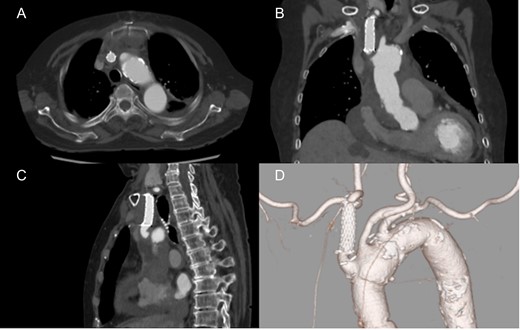

An 86-year-old woman with acute type A aortic dissection was transferred to our institution. Contrast enhanced computed tomography (CT) showed aortic dissection involving the ascending aorta extending to the proximal descending aorta. The true lumen of the brachiocephalic artery was occluded by the false lumen (Fig. 1). No neurological symptoms were present preoperatively. The patient was transferred to the operating room, and underwent central aortic repair with ascending aortic and bicaval cannulations. Cerebral perfusion was monitored with near-infrared spectroscopy (INVOS cerebral oximeter, Somanetics Inc, Troy, USA) and transcutaneous carotid echo. Inside the aorta, the orifice of the brachiocephalic artery was completely occluded by the false lumen. Selective cerebral perfusion (SCP) through the brachiocephalic artery was initiated immediately, however, the SCP flow was not sufficient due to stenotic lesion with low right side regional oxygen saturation (rSO2). Considering low rSO2, it was felt that the lesion should be treated even without preoperative neurological symptoms. The S.M.A.R.T. Vascular Stent System (Cordis Corp, Fremont, CA, USA) (12 mm × 40 mm) was inserted and deployed inside the brachiocephalic artery. After SCP cannula was inserted through the stent, right side rSO2 increased similar to the left side. Finally, ascending aortic replacement by using 26 mm J-Graft (Japan Lifeline Co., Ltd., Tokyo, Japan) was performed. Postoperative course was uneventful without any neurological event. Postoperative CT scan showed good stent patency and no residual dissection in the brachiocephalic artery (Fig. 2).

Preoperative computed tomography findings. Axial (A), coronal (B) and sagittal view (C). 3D computed tomography angiography (D). The brachiocephalic artery was occluded by the false lumen.